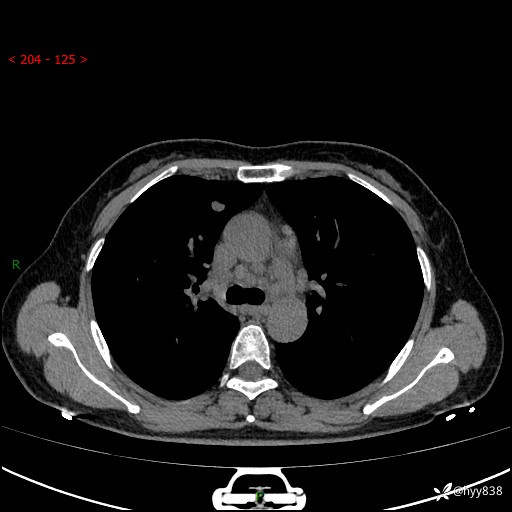

【患者信息】:58岁/女

【主诉】:体检发现肺结节

【检查】:胸部CT平扫+增强

结节病 (44)

小细胞癌 (19)